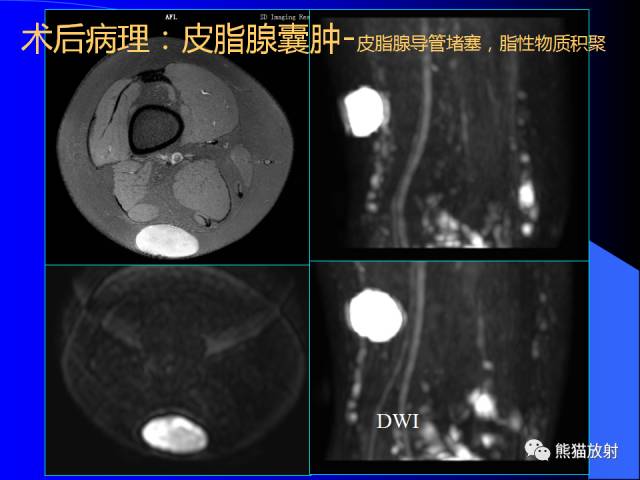

膝关节周围囊肿是较常见的病变,可以是原发的,多见于青年及儿童,囊内容物通常是黏液;也可以是继发的,多与关节腔相通,内含一般黏性的滑液,常继发于膝关节骨关节炎、类风湿关节炎、非特异性滑膜炎、半月板损伤、髌骨软骨软化症等。